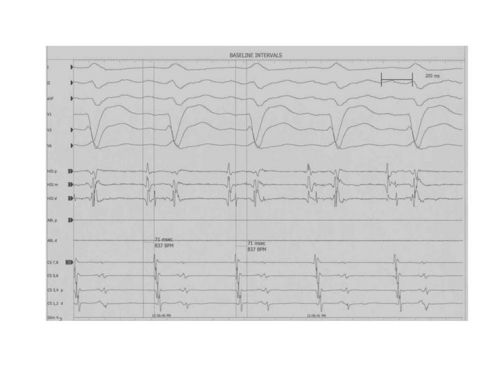

Pseudo V-A-A-V response

A pseudo VAAV response can occur when performing the Ventricular Overdrive Maneuver in patients with a long HV interval.(See Figure Below) This is why is important to include the His deflection in your tracings. In the figure below, the Ventricular Overdrive Maneuver resulted in a VAAHV response. This response can be seen in

- AVNRT and AVRT when the baseline HV interval is prolonged (as in this case) or

- When VOD pacing results in a VA on the slow pathway and the first A after termination of ventricular pacing is from the second to last ventricular paced beat.